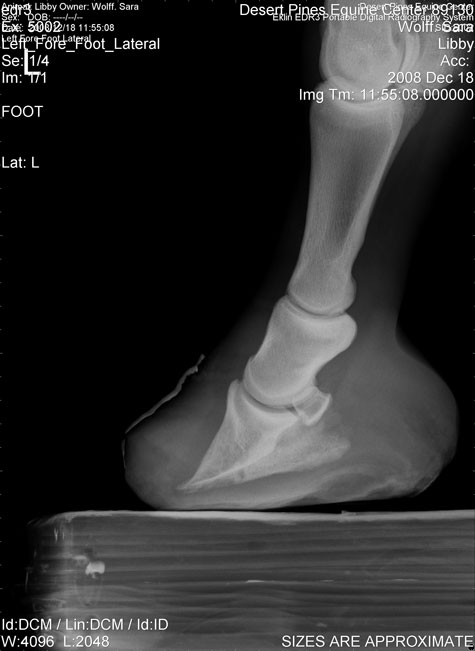

Posted on Thursday, Dec 18, 2008 - 9:56 pm: I just walked in the door and am waiting my turn in the shower while having a glass of wine. A long trip, but uneventful, luckily. After the first 30 mi. the roads weren't bad.The news is good (I think) Libby doesn't have an active case of laminitis and Dr. Lamb doesn't think she's had a reoccurance since her original severe episode. There has been no further rotation. Her problem is her lack of new foot growth and the toe of her sole is extremely painful, especially on the inside of it (is that medial side?) She was being treated as if she was having laminitis with her heel being raised. When looking at the position of her coffin bone in a regular x-ray you would think she needed her heel raised. After taking several digital x-rays, Dr. Lamb tried various combinations of pads and boots and wound up putting an ultra boot on her with the wedging removed, then filling it with a really soft silicone impression type material that forms to the foot and hardens, but remains very cushey. After it set, he cut out the area under the toe. He also put some really soft stuff right at the toe under the silicone pad which lifts the sore area so it isn't getting any pressure put on it. She goes back on the 30th. The boot should stay on her until then and she remains stalled in a heavily bedded stall. She handled the trip fine and was very happy to get home again; I think she was afraid she was going to miss dinner and was overjoyed to see it waiting for her. She was moving quite a bit better when I unloaded her, although still sore. She was feeling good enough that she pranced a little on the way from trailer to barn, so I feel progress has been made. I'll keep you posted. I'm ready for a second glass of wine and a shower. I stopped about an hour from home for a burger (first meal of the day!) and let Libby eat a little grass hay and rest while a ate. I think it's going to be an early night! |

Posted on Friday, Jan 2, 2009 - 3:57 pm: Finally, here are pictures the vet took at her first visit on Dec. 18th. You can see the "before" xray,which is at the bottom left, and the "after" where Dr. Lamb had added an injectable padding and a wedge. He first made a pad from the injectable material, took it off and trimmed out the front part of the sole on the pad, then fitted the pad to her foot. Then the plastic wedge and plastic boot were added. The boot was only vet wrapped and taped on so we could adjust the height of the pad if necessary. She would up with about a 3 degree heel wedge.The foot with the nailed on shoe is the foot on the leg with the tendon injury.

Posted on Friday, Jan 2, 2009 - 4:10 pm: Libby has very little sole, as you can see. However, her foot was finally able to be pared down to where there is nothing but healthy tissue, so the vet feels it will grow.I took Libby back to Dr. Lamb on the 30th of January, and her pad and boot were removed, she was checked and xrayed. My farrier met me down there and he and the vet were able to trim her heel down just a hair more, then remade the padding and put her in a glue on boot which should stay on for 5 or 6 weeks. Her palmer angle is a little closer to where it should be now; I think Dr. Lamb said he was able to improve it by another degree, but I'm sorry I don't remember for sure. The boot, wedge and padding can be removed if she gets sore and the pad and wedging adjusted if we feel it needs to be. When she arrived at the vet's, even after a 3+hr trailer ride, she was walking pretty good. There is some unevenness in her gait, which in part, I think, is due to the fact that her left and right front shoes are now not at the same height. She wasn't sore at all when the hoof tester was used! We are handwalking her again for 10 mins. twice a day. I think she could be turned out in her pen, but there is just too much ice to risk it right now. She is getting pretty bouncy when being hand walked, so I know she's feeling much better. She is also off bute now. The farrier is coming first of the week to redo her other shoe and to trim her hinds. We wanted to give her a chance to get used to the new pad and boot before asking her to stand on it while her other front foot was worked on. btw, you can see in the xrays how her "good" foot on the injured leg was affected by not having weight on it for so long. It is much more narrow than her original foot. She is shod with a shoe that gives a lot of rim support and heel width in hopes her foot will eventually expand. |

| Moderator: DrO |

Posted on Saturday, Jan 3, 2009 - 10:06 am: Sara, one change I don't like, and am uncertain why it was done, is all the "toe" added out in front of the coffin bone. Though I do see a slight rocker to help I think less material out front would help Libby's break over. Does the veterinarian explain this?DrO |

Posted on Saturday, Jan 3, 2009 - 10:59 am: I think he was trying to pad the front of her foot as that was where she was especially tender, but I'm not sure. After the xray was taken, he did remove some of it. I think that when he put the boot on, she may have pushed some of the padding forward. On her last visit, he removed all the padding in the front. It just goes under her heels and around under the hoof wall where it is very thin. It is removed totally under her sole. The effect is to lift the sole up a little and to put pressure on the heel and under the hoof wall. She still is moving much, much better than she was, even off the bute. |

Posted on Saturday, Jan 3, 2009 - 1:21 pm: In "real life" Julie, I don't think there is much hoof in front of the breakover. Due to the founder, her hoof is trimmed back to just the sole and under structures of the hoof; there isn't nay extra hoof wall there at all. This is one of her problems; there is very little actual hoof to work with. What you are seeing in the top two pictures is the hard plastic boot and the padding the vet put in to protect her foot.(If we are talking about the same thing? I'm not sure we are.) |